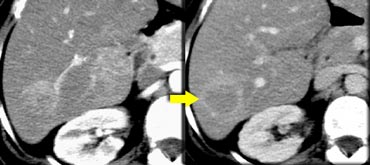

The case on the left demonstrates how difficult the detection of ta cholangiocarcinoma can be.

Only on the delayed images at 8-10 minutes after contrast injection a relative hyperdense lesion is seen. This is the fibrous component of the tumor.